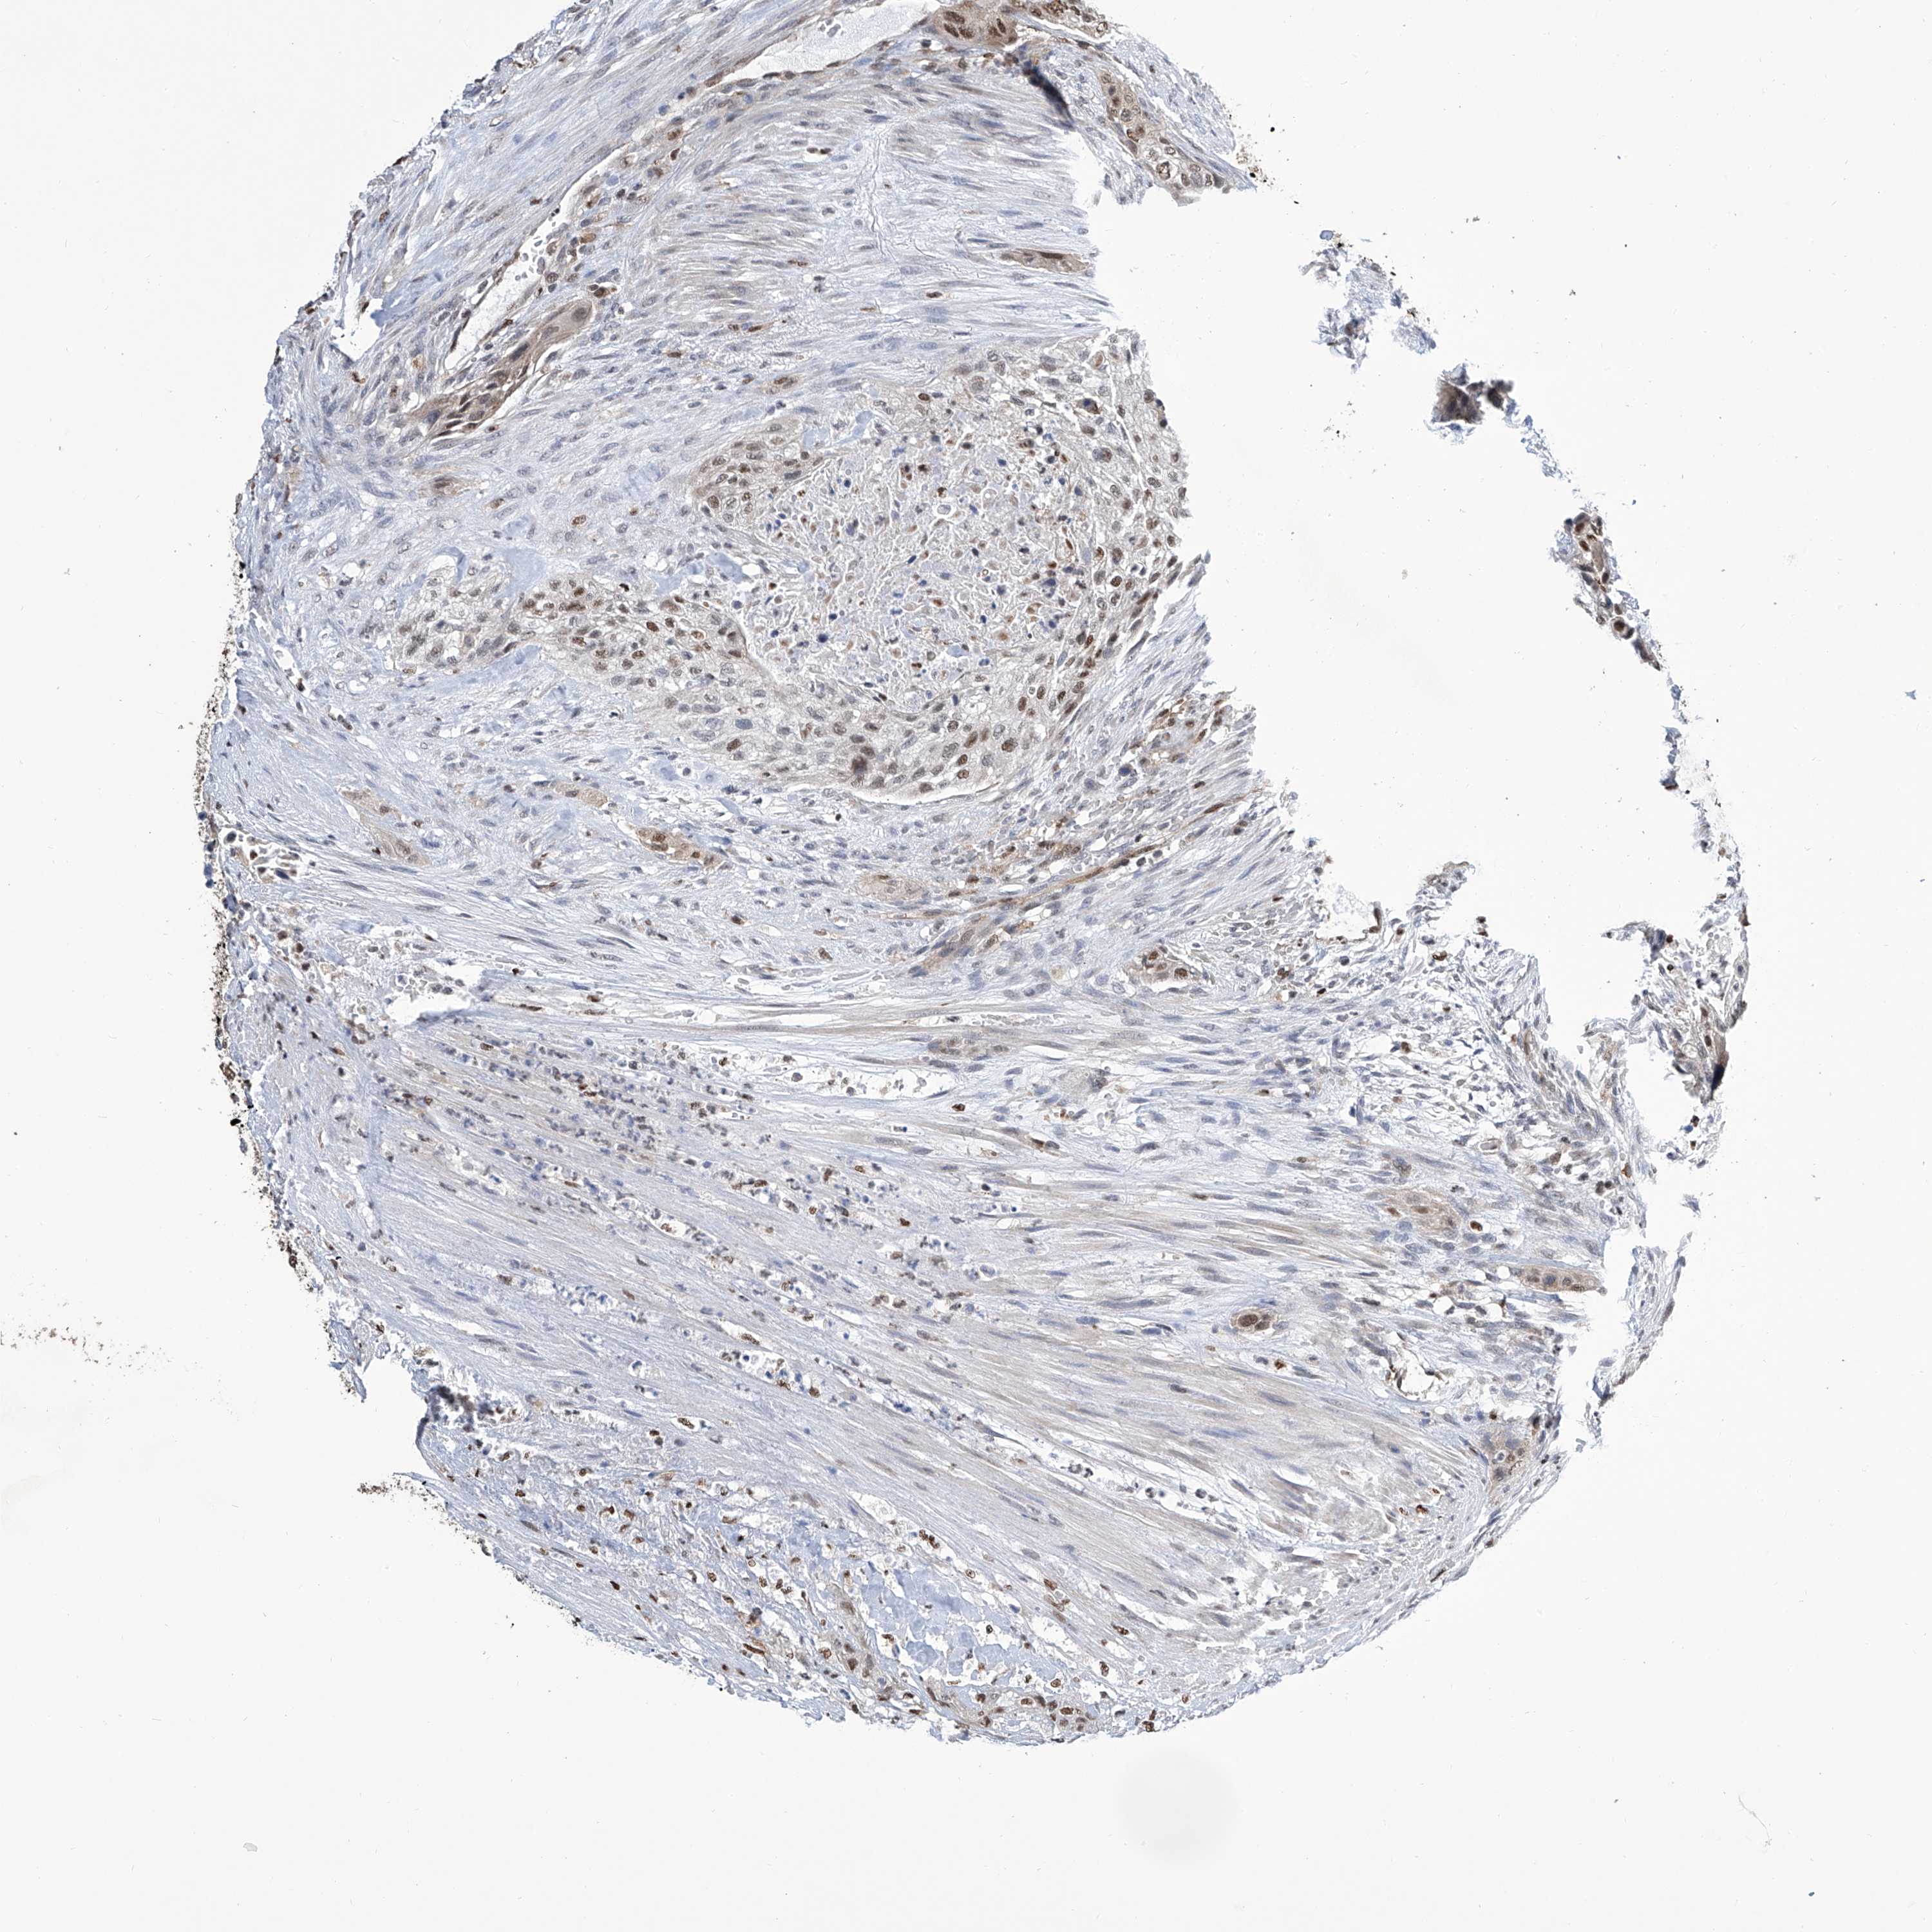

UROTHELIAL CANCER - Protein expressioni

A mouse-over function shows sample information and annotation data. Click on an image to view it in a full screen mode. Samples can be filtered based on level of antibody staining by selecting one or several of the following categories: high, medium, low and not detected. The assay and annotation is described here.

Note that samples used for immunohistochemistry by the Human Protein Atlas do not correspond to samples in the TCGA dataset.

Antibody stainingi

Antibody staining in the annotated cell types in the current human tissue is reported as not detected, low, medium, or high, based on conventional immunohistochemistry profiling in selected tissues. This score is based on the combination of the staining intensity and fraction of stained cells.

Each image is clickable and will lead to virtual microscopy that enables deeper exploration of all samples and also displays staining intensity scores, fraction scores and subcellular localization as well as patient and tissue information for each sample.

Antibody HPA031962

Staining

High

Medium

Low

Not detected

Intensity

Strong

Moderate

Weak

Negative

Quantity

>75%

75%-25%

<25%

None

Location

Nuclear

Cytoplasmic/membranous

Cytoplasmic/membranous,nuclear

Urothelial carcinoma, Low grade

Urothelial carcinoma, High grade